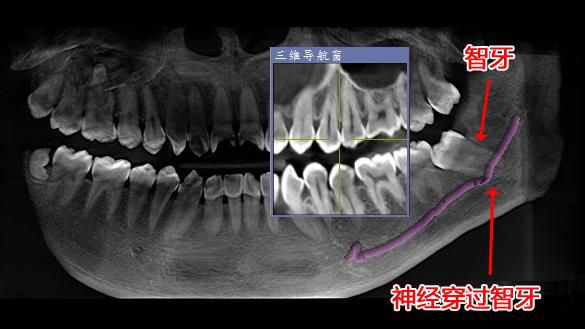

應用案例一:

△經西諾德3D口腔全景CT檢查發現神經穿過智牙。

爲預防神經損傷,拔除智牙前,有必要先通過口腔全景CT了解牙根與下颌神經管的關系。如盲目操作易損傷神經,出現下唇及颏部皮膚不完全性麻木或兼有燒灼、刺痛、蟻走等異常感。